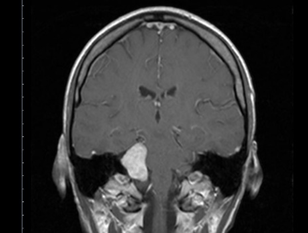

After having flashes of blurred vision and increasing headaches in the evenings after work, I thought I might need glasses and went for a routine eye test. The opticians referred me for an MRI after tests showed my visual field on the right-hand side was severely limited.

A few days later, I sat back up on the hospital bed after the MRI and was asked by the nurse if I had come to the hospital alone. Her question hit me like a bullet. What I thought was just a standard check-up, ended up being devastating news.

The MRI revealed a ‘large and significant’ mass on my brain which the neurosurgeon later confirmed was a meningioma brain tumour. I was told that surgery was the only option and that due it’s size and location, the procedure would be complicated and potentially life threatening. The surgeon warned that he would not be able to remove all of the tumour, and that I needed to prepare for a long journey.

After a lengthy surgery of 14 hours, the team had to eventually stop for a break. The tumour measured 5cm x 5cm and had been steadily growing for 10 to 15 years, encroaching on my optic nerve, carotid artery and pituitary gland. The surgeon explained they will need to go in and operate again to continue to remove as much as possible. I returned home to rest and reset, ready for round two a couple of weeks later. It was really difficult knowing I had to face going through it all again, not knowing if I’d wake up, wondering what my quality of life would be like after all the risks and side effects I’d been warned of after brain surgery.